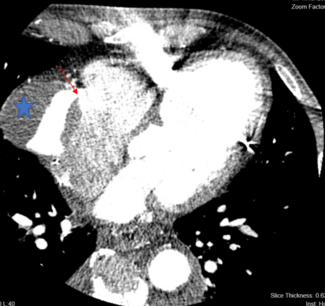

Lina Ya'Quob, MD; Richard K. Cheng, MD, MS; Marc Simon, MD; Harsh Argawal, MD

A 71-year-old man with history of coronary artery disease status post coronary artery bypass grafting in 1999 presented with decompensated heart failure.